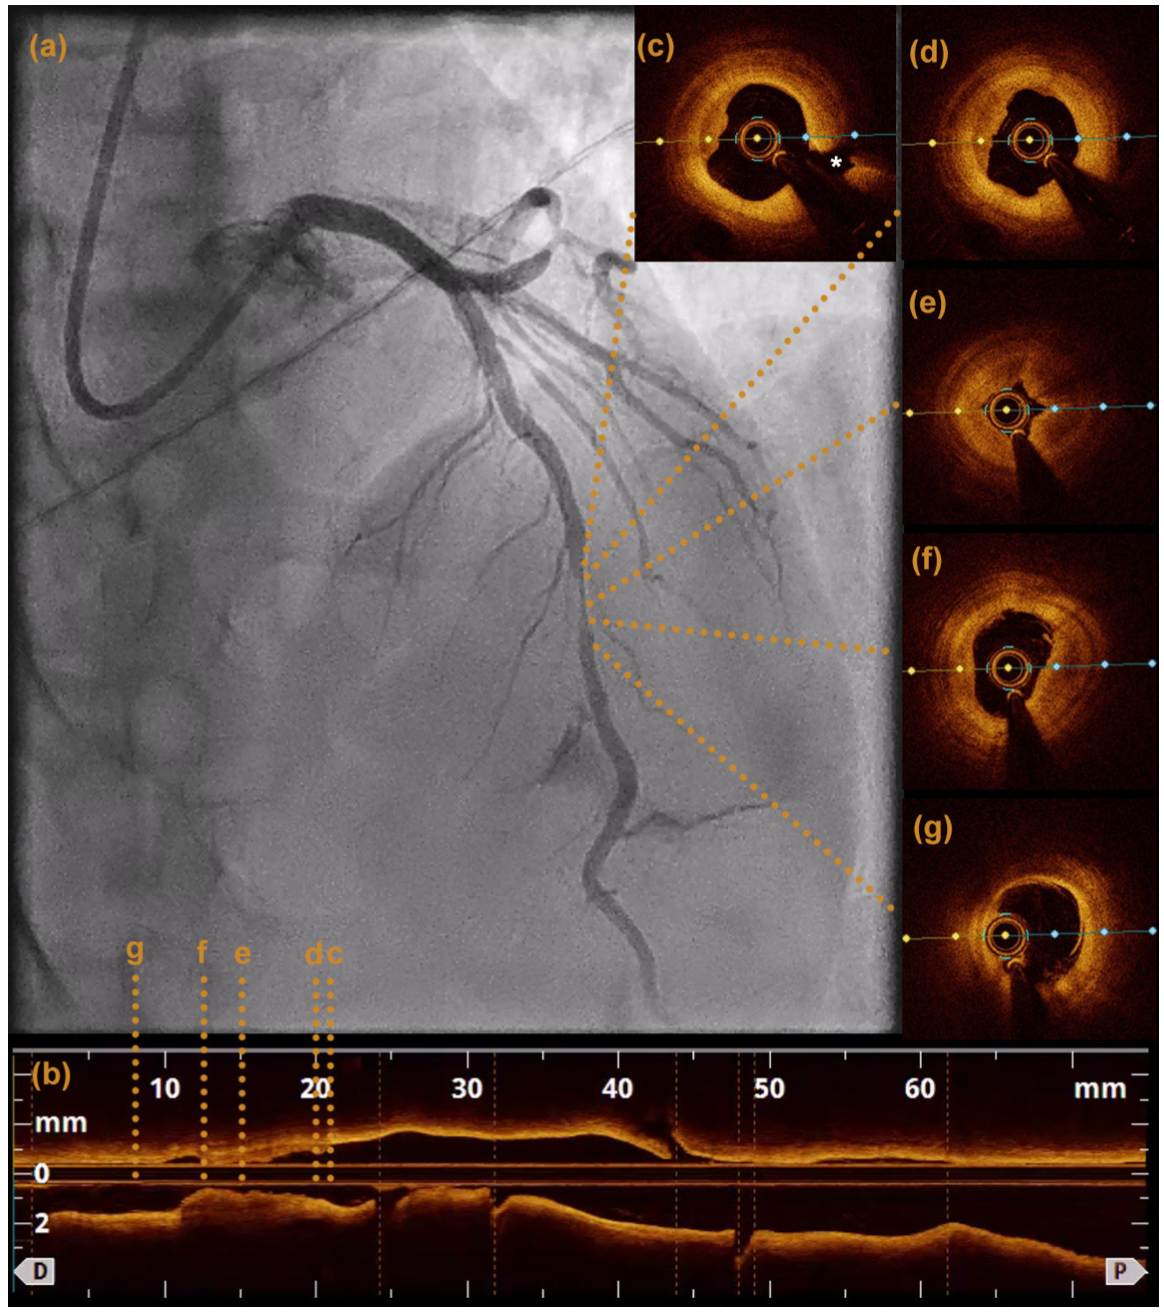

A 63-year-old male with a history significant for 50 pack years of tobacco use and a cerebrovascular accident presented with unstable angina. His electrocardiogram (ECG) showed sinus bradycardia with nonspecific ST/T wave changes (Figure 1A). Coronary angiography demonstrated significant myocardial bridging of the mid left anterior descending artery (LAD) (Video 1 and Figure 2) and nonobstructive coronary artery disease (CAD) otherwise. His left circumflex (LCX) CAD was physiologically insignificant on assessment with instantaneous wave-free ratio (Figure 3). The following day, the patient developed transient anterior ST-segment elevation myocardial infarction with a troponin of 0.5 ng/mL (Figure 1B). He was brought back for coronary angiography with intracoronary imaging. His baseline angiogram was unchanged and optical coherence tomography (OCT) was performed in the LAD, which showed evidence of acute plaque rupture within the myocardial bridging segment (Video 2 and Figure 4). There was a concern for stenting the bridging segment due to reported higher rates of target-lesion revascularization and concerns of stent thrombosis, stent fracture, and coronary perforation. Therefore, cardiothoracic surgery was consulted for unroofing of the mid LAD or surgical bypass, which are generally considered safe and effective.1,2 The left internal mammary artery was found to be a poor conduit in the operating room due to size and flow limitation. Given that the patient already had a median sternotomy, surgical revascularization with saphenous vein grafting and surgical myotomy to relieve the systolic compression were performed. The latter would facilitate durable percutaneous revascularization options in the future.

This case of acute plaque rupture within a myocardial bridging segment demonstrates the importance of performing hemodynamic assessment of intermediate-appearing coronary lesions, as well as utilizing intracoronary imaging to characterize coronary lesions and aid in selecting the appropriate treatment plan.